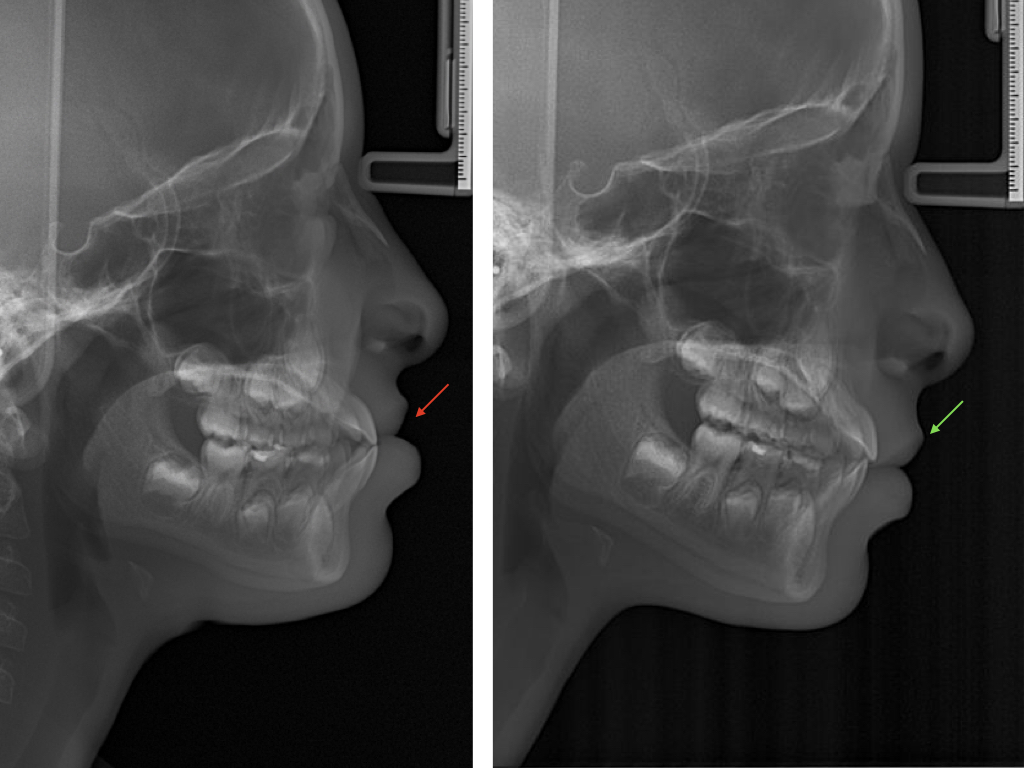

NUUMOON En images Arrêt des parafonctions (lolette, pouces, etc…) Orthodontie pédiatrique Orthopédie dento-faciale Apnée du sommeil de l’enfant (TROS) Esthétique du sourire Orthodontie et Articulation Temporo Mandibulaire (ATM) Traitement combiné ortho-chirurgicaux Traitements pluridisciplinaires Arrêt des parafonctions Effet de la lolette sur les dents Effet du pouce sur les dents Position de la langue et impact sur les dents Mieux respirer pour mieux grandir Respiration et santé Respiration et santé Sans titre.004 Orthodontie pédiatrique Conséquences ventilation orale – nuumoon ChatGPT Image 5 sept. 2025, 09_00_25 conséquences posturales de la ventilation orale Prévention canine incluse Prévention canine incluse Prévention canine incluse Dents qui s’emboitent à l’envers Dents qui s’emboitent à l’envers orthopédie dento-faciale Traitement déformation mâchoire Déformation des mâchoires : menton en avant Déformation des mâchoires : menton en avant Déformation machoire Déformation machoire Déformation machoire : machoire du bas en arrière Déformation des mâchoires : menton en avant Déformation des mâchoires : menton en avant Posture dents et mâchoire Anomalie de la mâchoire Apnée du sommeil orthodontie invisible à Genève Aligneurs transparents & bagues linguales – l’art de corriger sans rien laisser paraître Troubles de l’articulation temporo-mandibulaire et bruxisme Chirurgie orthognathique Traitements pluridisciplinaires INSIGHTS Contenu pour les enfants